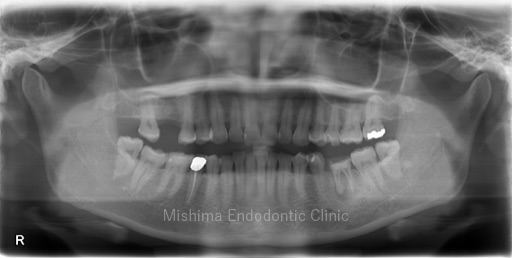

Before

| 治療内容 | 左上4が歯頚部よりカリエスを認めた。歯肉縁下カリエス、かつ、左上5の口蓋側への捻転により衛生管理が困難なため、左上4を抜歯し、左上5を保存することとした。 矯正は希望されなかったため、5→4に自家歯牙移植を行なった。 |